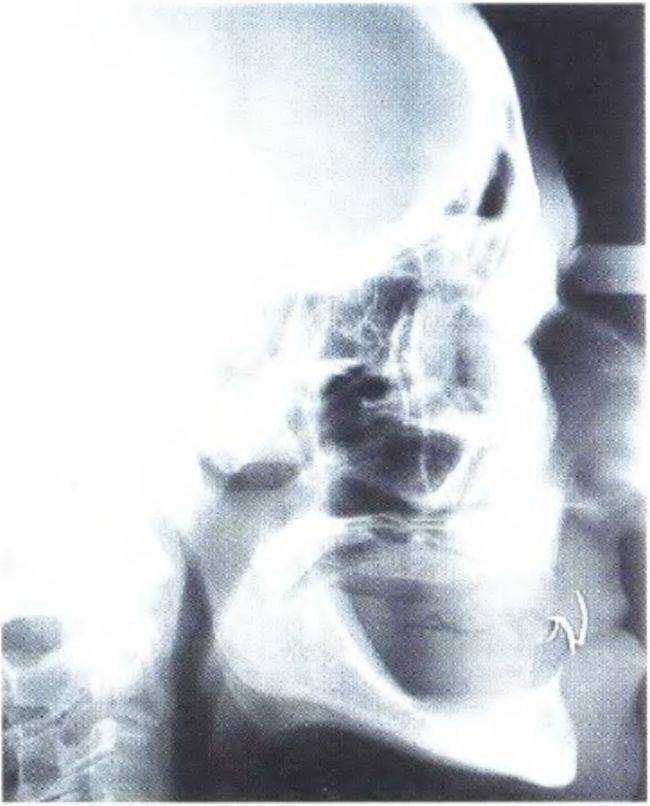

Рис. 3-44. «Среднесагиттальная томография» представляет собой участок боковой цефалограммы

Рис. 3-45а. На боковой цефалограмме визуализируются вестибулярные и небные контуры передних зубов, покрытых фольгой

Рис. 3-45Ь. Функциональный анализ цефалограммы

Одним из наиболее эффективных способов является боковая цефалограмма с фиксированной к передним зубам полоской свинцовой фольги (как описано ранее в данной главе и главе 6). Такой снимок позволяет провести анализ переднего отдела нижней и верхней челюсти, а также определить наклон имплантата и высоту кости. Кроме того, с помощью боковой цефалограммы можно выполнить сагиттальный функциональный анализ (рис. 3-45а и 3-45Ь). На рис. 3-46 представлены варианты сечения нижней челюсти в ее переднем отделе в зависимости от степени атрофии. Обычно плотность костной ткани в данном участке соответствует классу D1.